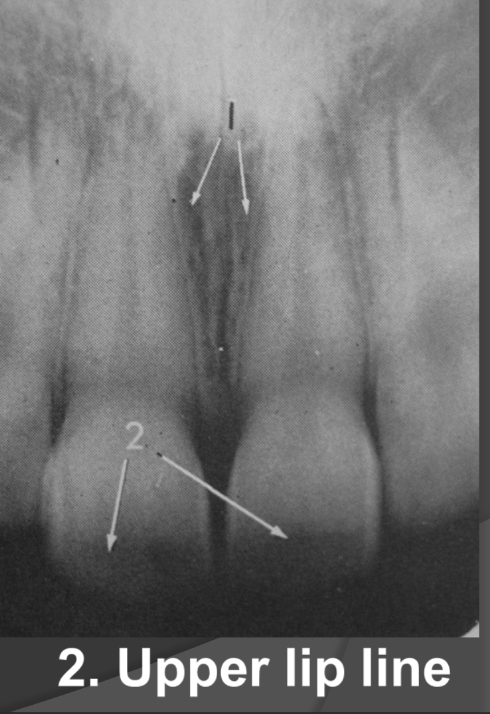

What does the lip line look like in a radiographic image?

-Radiolucent

-Horizontal line that runs across the central incisors usually